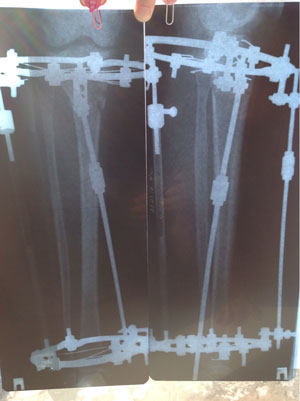

Рентген в 2 месяца.

Сращение идёт отлично, снятие аппаратов в 3 месяца!